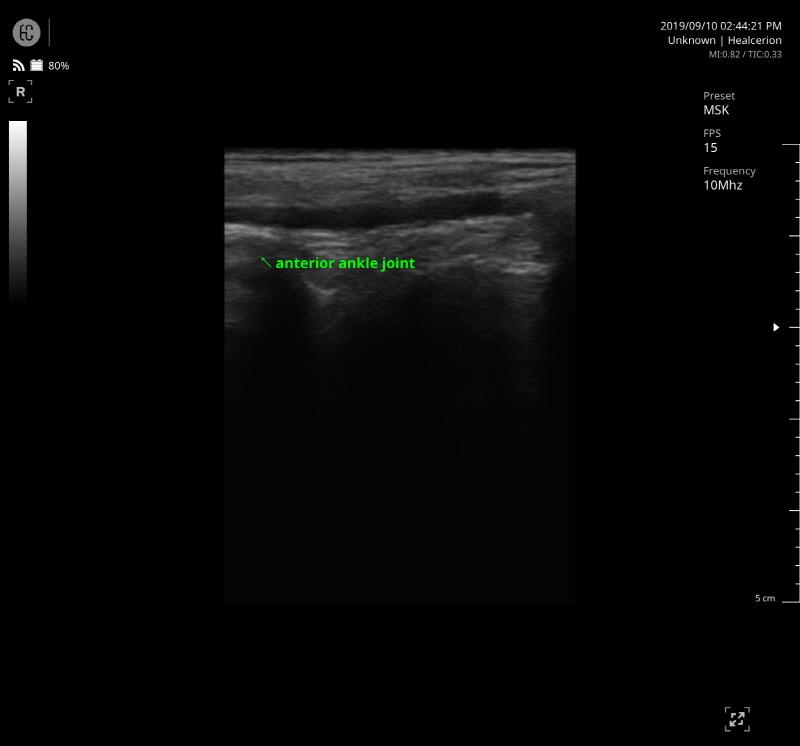

SONON 300L ecografía 1 SONON 300L ecografía 2 SONON 300L ecografía 3